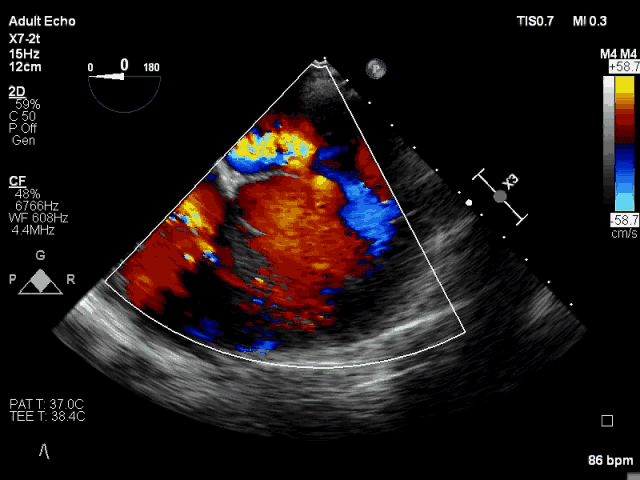

術(shù)前TEE CDFI示MR重度

此次手術(shù)直播患者為86歲老年女性,體重僅40Kg,二尖瓣后葉P2和P’1脫垂,極重度二尖瓣反流,同時(shí)合并重度肺動(dòng)脈高壓、中重度三尖瓣反流,STS評分11.05%,外科手術(shù)非常高危?;颊叨獍旰笕~主腱索斷裂,連枷鎖間隙大,使用國外同類器械可能難以完成手術(shù)。